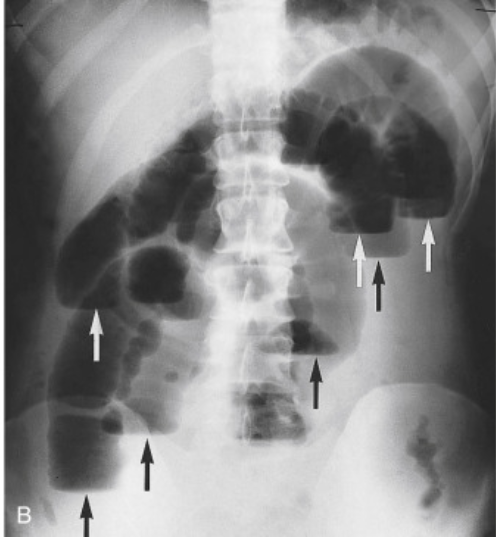

What does this x-ray show?

Note: erect abdominal films are rarely taken nowadays